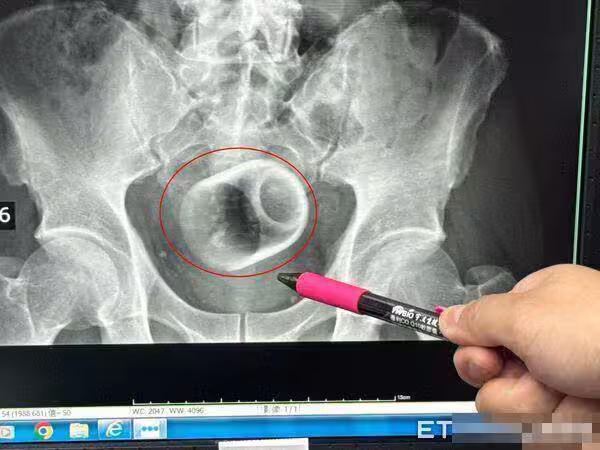

台中男3天便不出來!開腸剖出「8cm瓷杯」……醫者傻眼「怎麼進去的?」,本人低聲回答全場臉紅

吳坤達指出,回顧塞進異物,一般臨床上是基於好奇或想要尋求刺激,聽過有塞疫苗、瘧疾、椰子,但都有可能造成回顧胃腸收縮而失禁,甚至讓腸子窒息、破裂,還有可能引發腹腔感染,以及腹膜炎,有致死亡危機,萬一受傷,恐群要造口裝填肛門,才能引發腹腔感染,以及腹膜炎,有致死亡危機,萬一受傷,恐群要造口裝入便